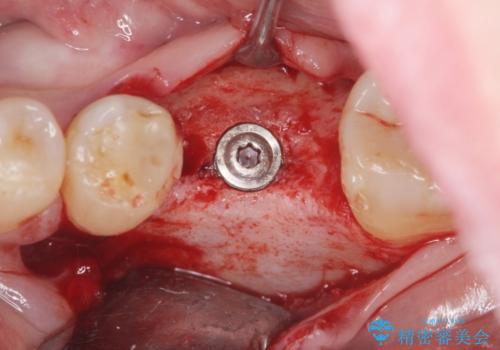

- 歯を破折により失い、インプラント治療を希望され来院されました。

インプラントを埋入し咬合機能を回復するとともに周囲の骨造成も同時に行っていきます。

インプラントを適切な位置に埋入することで、清掃性が高くしっかりと咬合力に耐えられるようなインプラント治療を行うことができます。